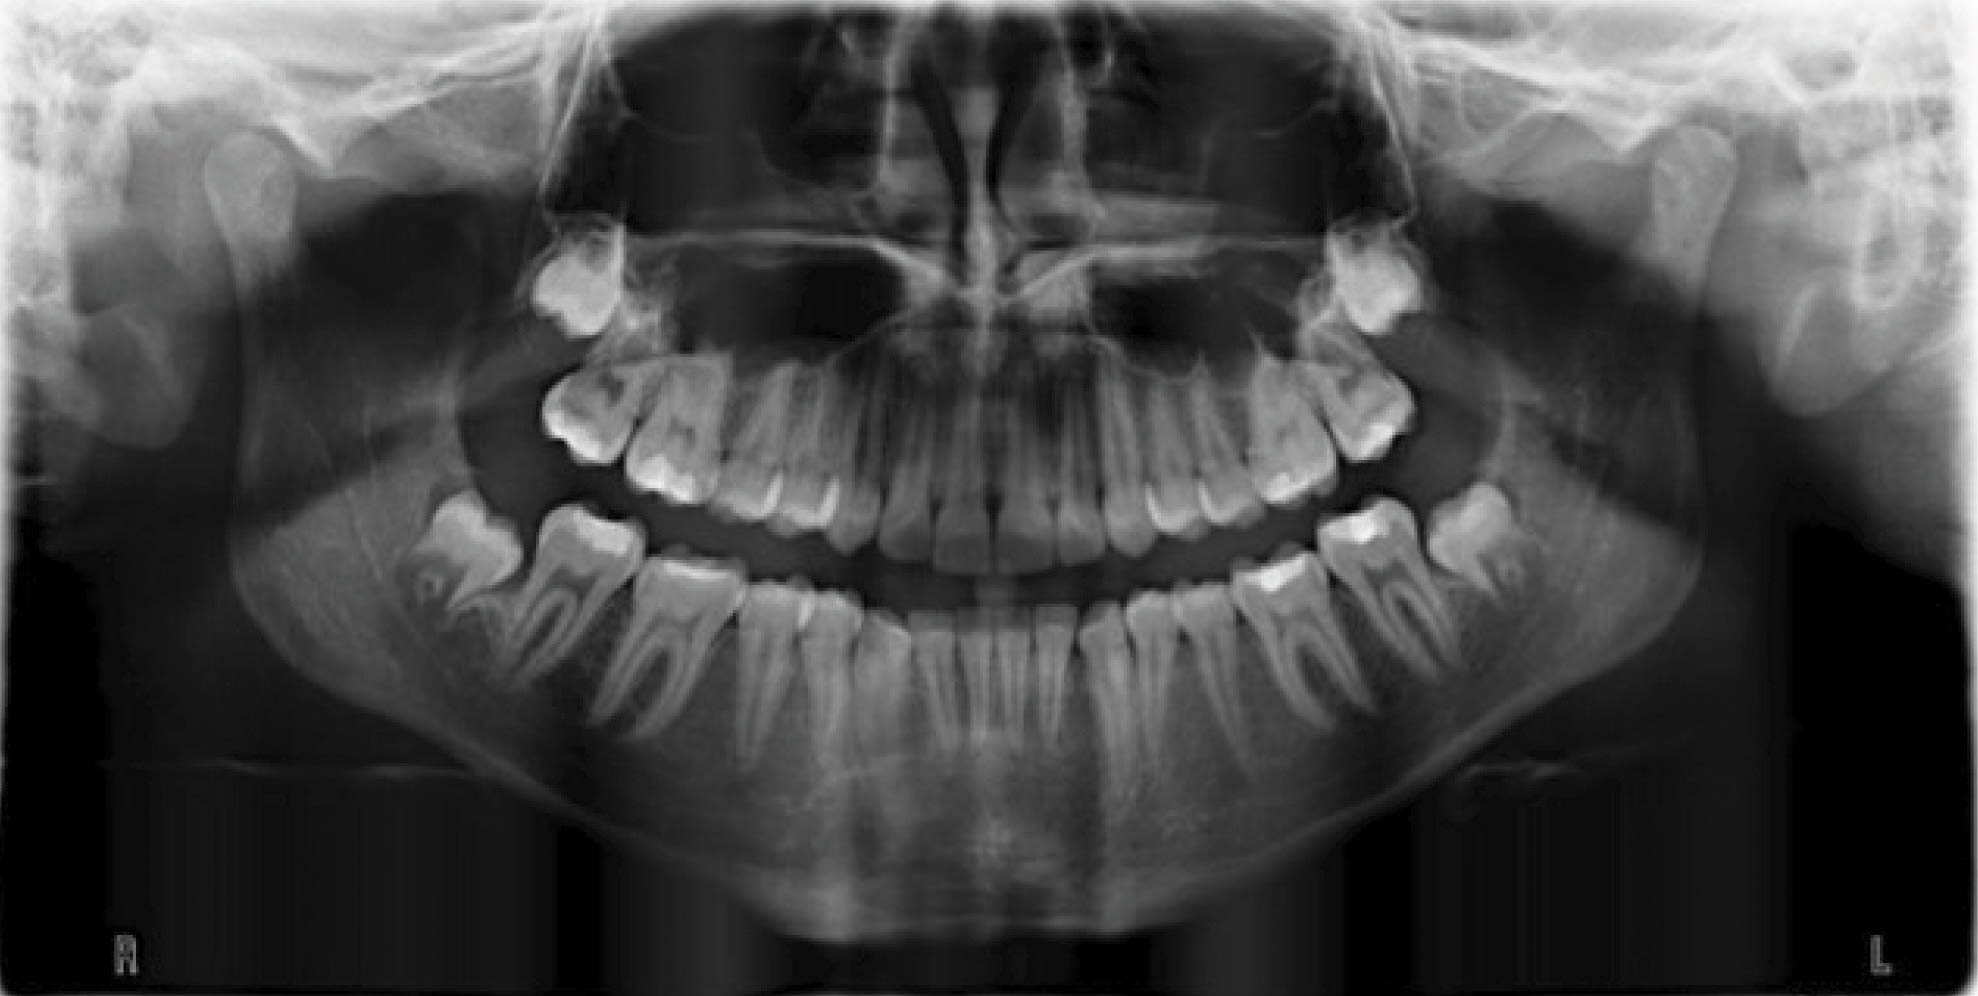

بیمار بعدی دختر ۱۲ ساله در مرحله اواخر میکس دنتیشن (شکلهای 92-۶ الی 94-۶) با اکلوژن ClII/1 است، دیپ بایت و کرادینگ دو فک دارد و لینگوالی شدن دندانهای قدامی بالا و پایین مشخص است. در (شکل 92-۶) هر دو لترال پایین را مشاهده میکنید که بلاک شدهاند. در OPG چیز خاصی مشاهده نمیشود و در لترال سفالومتری ارتفاع عمودی صورت کمی کاهش یافته و انسیزورها رترود شدهاند.

شکل 92-6

شکل 93-6

شکل 94-6

بخاطر در حال رشد بودن بیمار، استفاده از الاستیک کلاسII باعث اصلاح اکلوژن میشود. اصلاح کرادینگ با اکسپنشن خلف و پروترود نمودن قدام انجام میشود. اصلاح دیپ بایت به صورت نسبی و با پروترود شدن قدام انجام میگیرد.

در انتهای درمان هم کرادینگ خوب درمان شد و هم رابطه مولری درست گردید (شکلهای 95-۶ الی 97-۶). عکس OPG طبیعی و سوپرایمپوز نمودن عکسهای لترال سفالومتری نشاندهنده پروترود شدن انسیزورهای بالا و پایین میباشد.

نکته: همانطور که در مقالات در اول مبحث بیان شد، موقعیت مولر بالا و نقطه A در طول درمان فرقی نمیکند. این تغییرات مانند استفاده از هدگیر است در حالیکه با الاستیک کلاسII بدست آوردهایم. ضمناً رشد مندیبل و قدامیتر قرار گرفتن نقطه پوگونیون هم مشخص میباشد و منجر به کاهش تحدب صورت گردیده است.

نتیجه: طول درمان ۲۸ ماه با دو قالبگیری مجدد و الاستیک کلاسII ۲ انسی بود.